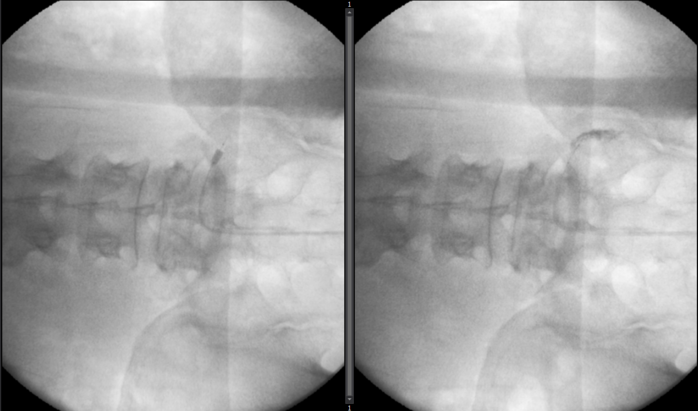

| ▲ 요추관협착증 치료 사진 |

수술적 치료는 내시경이나 현미경을 이용한 단순 감압술에서부터 나사못 고정술 (요추 유합술), 장분절 고정술 (척추 변형 교정술)까지 다양한 방법이 있으며, 이는 환자의 나이 및 증상의 정도, 디스크 및 협착의 정도 및 범위, 직립 x-ray에서의 척추 만곡, 골밀도 정도 등의 여러가지 인자들을 종합적으로 고려하여 결정하게 된다.